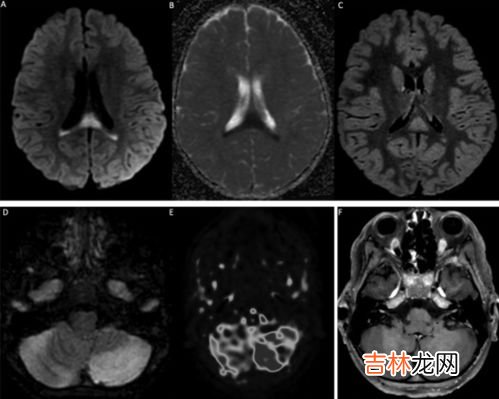

文章插图